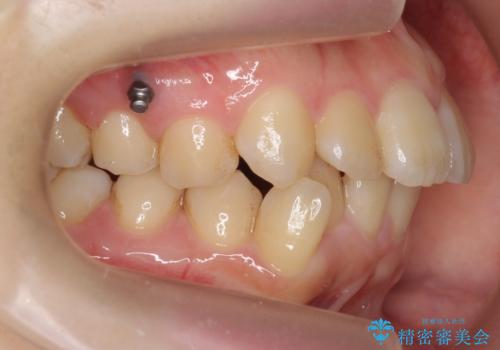

- 歯のがたつきを主訴に来院。

左右とも奥歯のがたつきがあり、左奥はすれ違っていました。

また、右奥は反対咬合になっていました。

患者様が気づかない範囲で妥協して終わるということをせず、しっかり奥歯に部分矯正を用いて大きな問題を解決してからインビザライン治療に入りました。